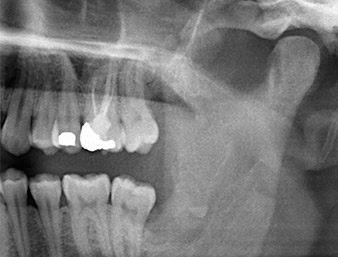

Un paziente di 26 anni lamentava dolori costanti e parestesia in seguito alla rimozione chirurgica di un dente del giudizio incluso. Le radiografie panoramiche hanno confermato la presenza di un residuo di radice collocato in stretta prossimità del nervo alveolare inferiore.

Il residuo di radice nella regione del dente 38 (LL8) mostrava già stretta vicinanza al nervo alveolare inferiore nell'ortopantomografia. La radice si era spezzata durante l'osteotomia ma non era stata rimossa dal dentista che aveva eseguito l'operazione a causa di dolore intraoperatorio. Per garantire il minor trauma possibile al tessuto, la nuova osteotomia doveva essere eseguita utilizzando un sistema piezochirurgico. Il paziente presentava un'anamnesi non rilevante e non era fumatore.